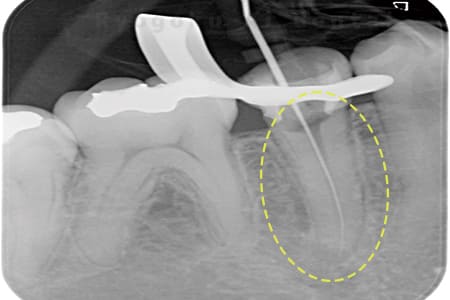

Case01

根管内の異物

- 原因

- 根管内異物(ファイル破折)による慢性根尖性歯周炎

- 治療期間

- 3ヶ月

- 治療内容

- マイクロスコープを使用した根管内異物除去並びにマイクロエンド

- 治療費用

- 121,000円(ファイル除去費用も込み)

他院で細い器具(ファイル)が根管内に破折した状態で、咬合痛を主訴に来院された患者様です。ファイルをマイクロスコープ下で除去し、根管治療を行ないました。

<リスク・副作用>

術後は痛み、腫れ、痺れなどの副作用が生じる場合があります。症状が再発する可能性があります。